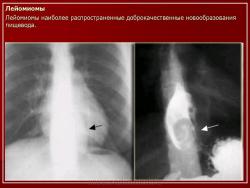

ПС. Пищевод. Набор изображений № 2. Новообразования пищевода. Варикозно расширенные вены пищевода. +

Пищевод.  Набор изображений № 2.